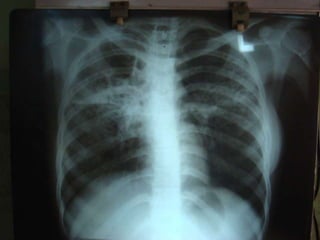

cxr

TRC Opinion(30/9/08): 	          Sputum AFB repeat neg; Sputum C/s for TB taken. Even though pt is sputum AFB negative with symptoms of  TB with  increasing infiltrates in CXR advice to con ATT-CatII Even after all these treatment measures pt continued with fever but breathlessness,Cough and expectoration subsided.pt advised to continue cat-II ATT until c&sreport arrives.